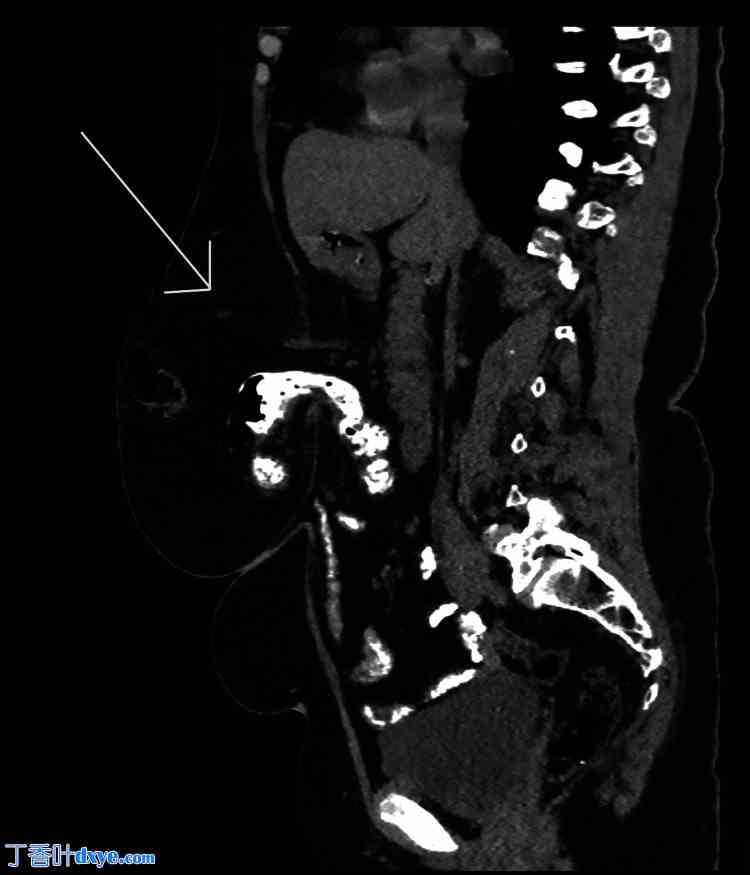

CT扫描(图1、图2)显示一个51毫米×36毫米的大型中线前腹壁缺损,伴有部分横结肠和大网膜疝出。鉴于疝气的症状性以及缺损处存在腹壁内容物,认为有必要进行手术干预以防止进一步的并发症。

图 2. 口服造影剂后非造影 CT 扫描的矢状面视图,显示疝囊内有肠管(箭头)。